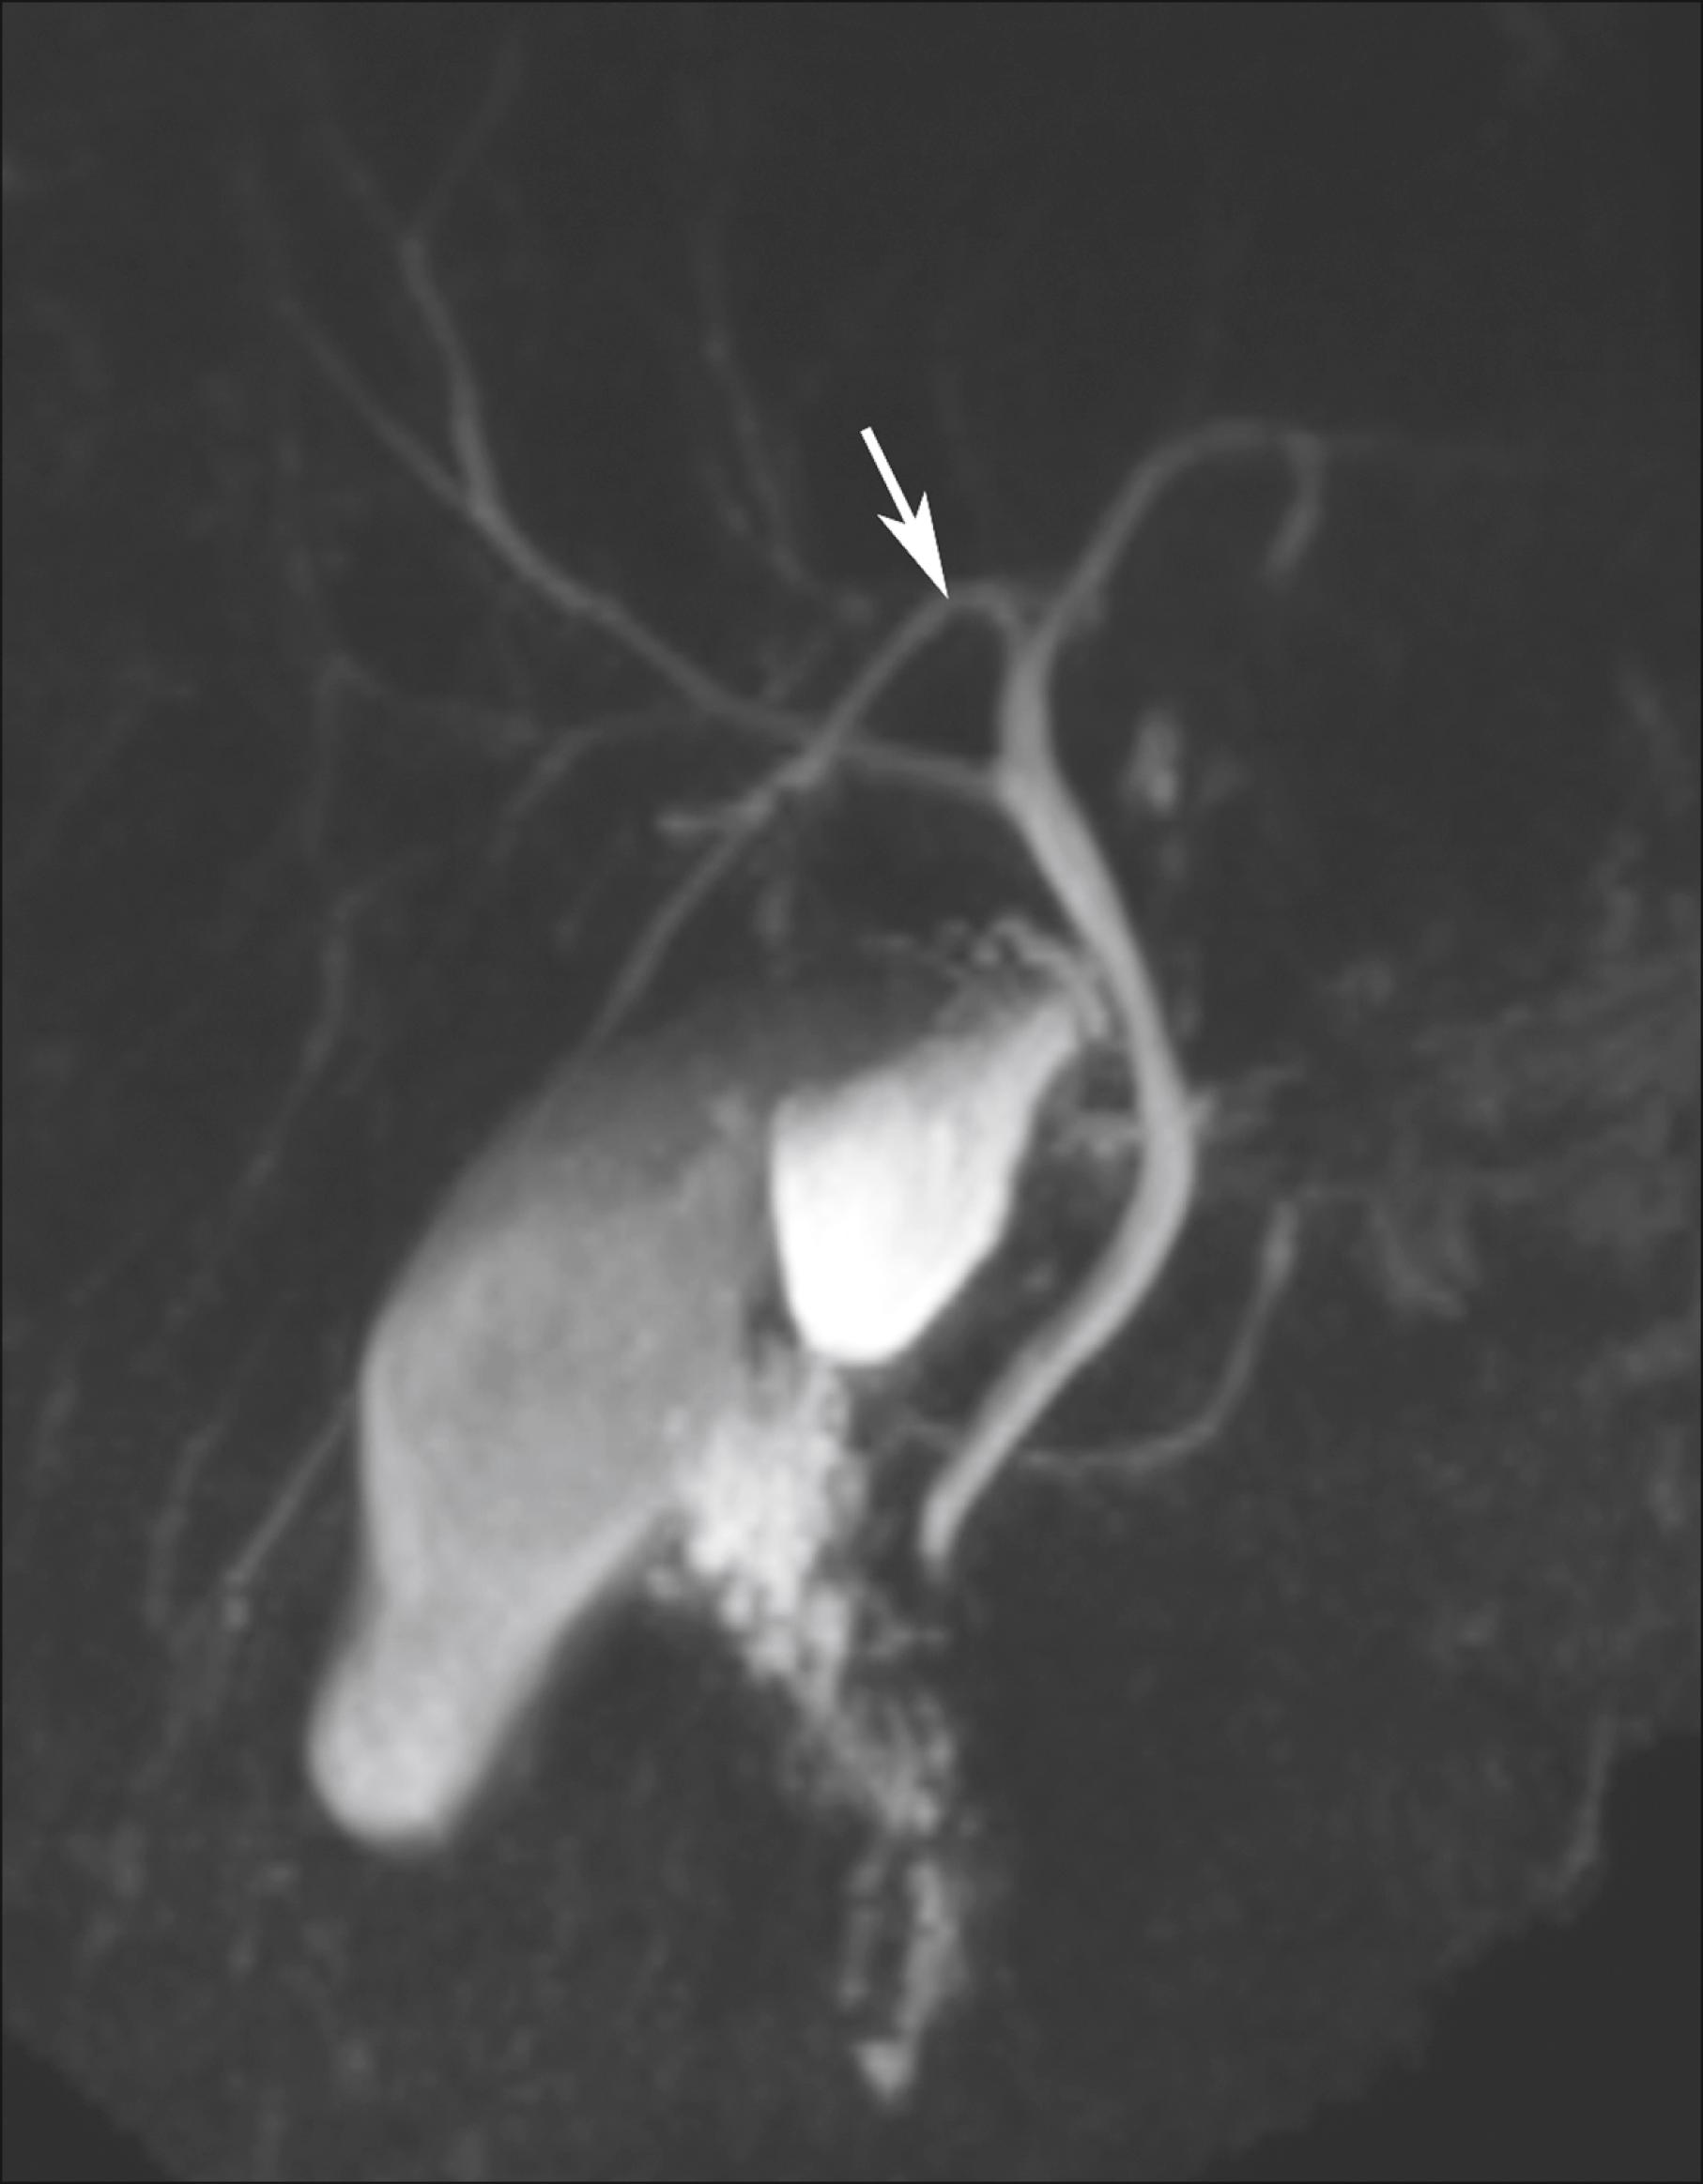

Fig. 67.6, Magnetic resonance cholangiopancreatogram showing the right posterior sectoral duct (arrow) draining into the left hepatic duct (type 3 intrahepatic duct drainage pattern).